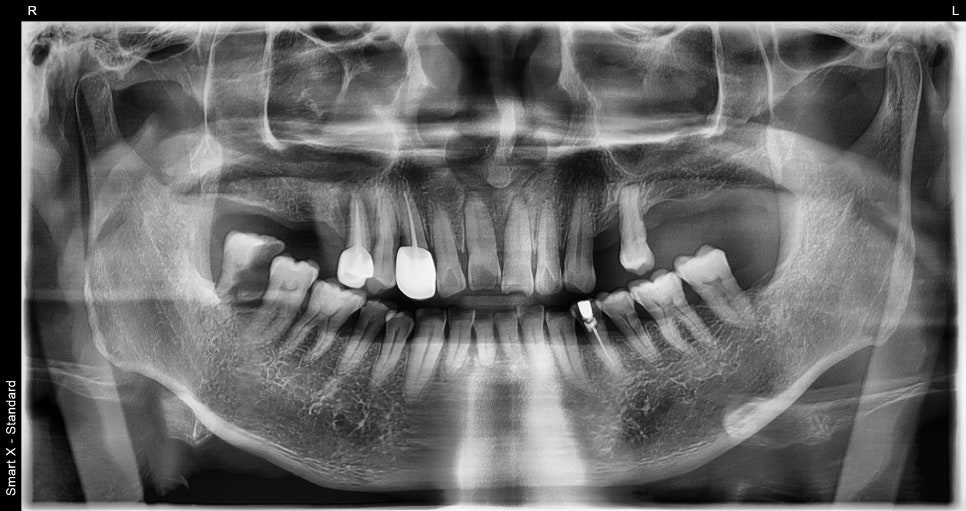

Full panoramic X-ray taken at the first visit

During the detailed diagnosis, in addition to the front tooth trauma, advanced decay and bone loss were found in the right molar area.

Ultimately, that area required extraction, and implant surgery began together with bone grafting.

From this point on, the case changed from a simple trauma to a complex treatment case that required managing the entire oral cavity.

🖼️ Scene from the start of implant surgery

X-ray immediately after implant surgery and the intraoral view after surgery

Before-and-after panoramic X-ray comparison (left: first visit / right: after treatment)